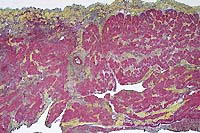

- Case 8-2. Otic vesicle, Brain. The otic vesicle is

heavily infiltrated by inflammatory cells and fibrin, and contains

a mineralized otolith. The connective tissue between the brain

and otic vesicle is similarly infitrated by abundant inflammatory

cells.

Brown

& Brehn, 40x obj

- Case 8-2 . Skull. Some macrophages in the exudate

surrounding the otic vesicle contain abundant Gram positive cocci.

20x

obj

- Case 8-2.Gill filaments and lamella. The interlamellar

space is partially filled between most gill lamella by an infiltrate

of macrophages, lymphocytes, and fewer mucus cells and/or epithelial